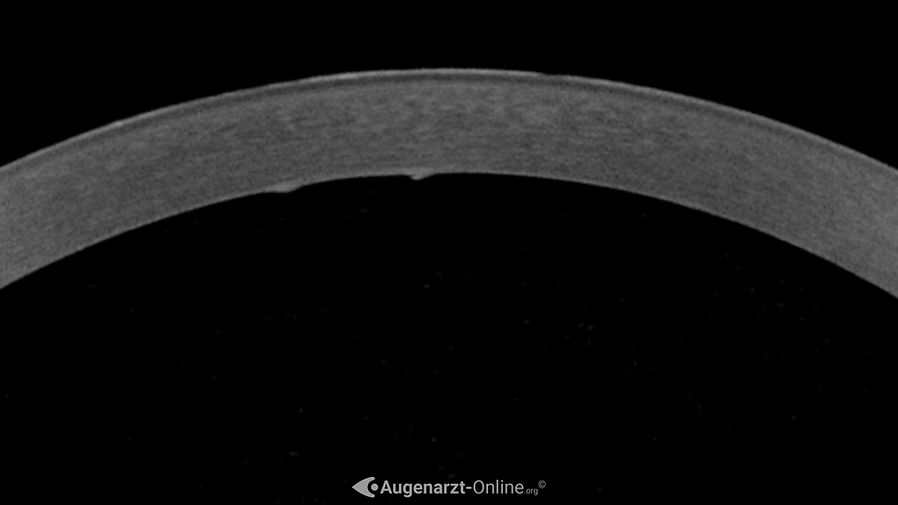

Haab'sche Linien

Zufallsbefund einer Ruptur der Descement Membran (Haab'sche Stria). Kein Trauma erinnerlich, kein vorausgegangener Glaukomanfall.

Foto einer Ruptur im Bereich der Descementmembran der Hornhaut (Haab's striae)